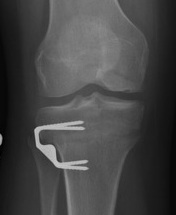

Pre and post OCA with HTO

Technique

Use CT to get appropriate size graft

Match curvature of radius of donor site

Press fit